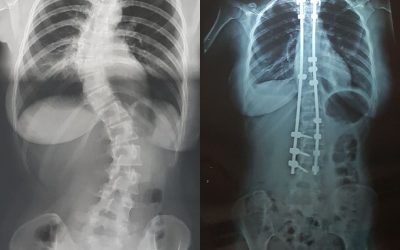

Mercredi 10 Juillet, J+5, la première radio et les douleurs.

A partir du mercredi se sont déclenchées des douleurs « bizarres » dans mes jambes, au niveau de mes cuisses. Nouvelles douleurs, inconnues jusqu’à présent. Je n’arrivais pas trop à changer la position de mon lit, en effet, je restais plus allongée que...

Les 6 premiers mois ont été plus ou moins compliqués. Je suis restée allongée tout l’été, pendant 2 mois à cause de mes jambes. Mon rendez-vous des 6 mois c’était bien passé, les greffes étaient bien, le matériel n’avait pas bougé, tout était en...

1 an post opératoire.

RENAISSANCE. Je ne souffre plus du dos, plus de douleurs. Je sais enfin ce que ça fait de ne pas avoir mal au dos, de vivre pleinement et normalement. Je ne regretterai jamais de m’être faite opérée, ma santé est améliorée, je vis normalement et je n’ai...

2 ans post opératoire.

WAHOU! 2 ans aujourd’hui que j’ai été opérée. Quelle fierté! Quand je repense aux souffrances, aux douleurs, aux pleurs, à ma colère, que je suis heureuse d’avoir réussi à parcourir tout ce chemin. J’ai repris le sport, je fais des activités...